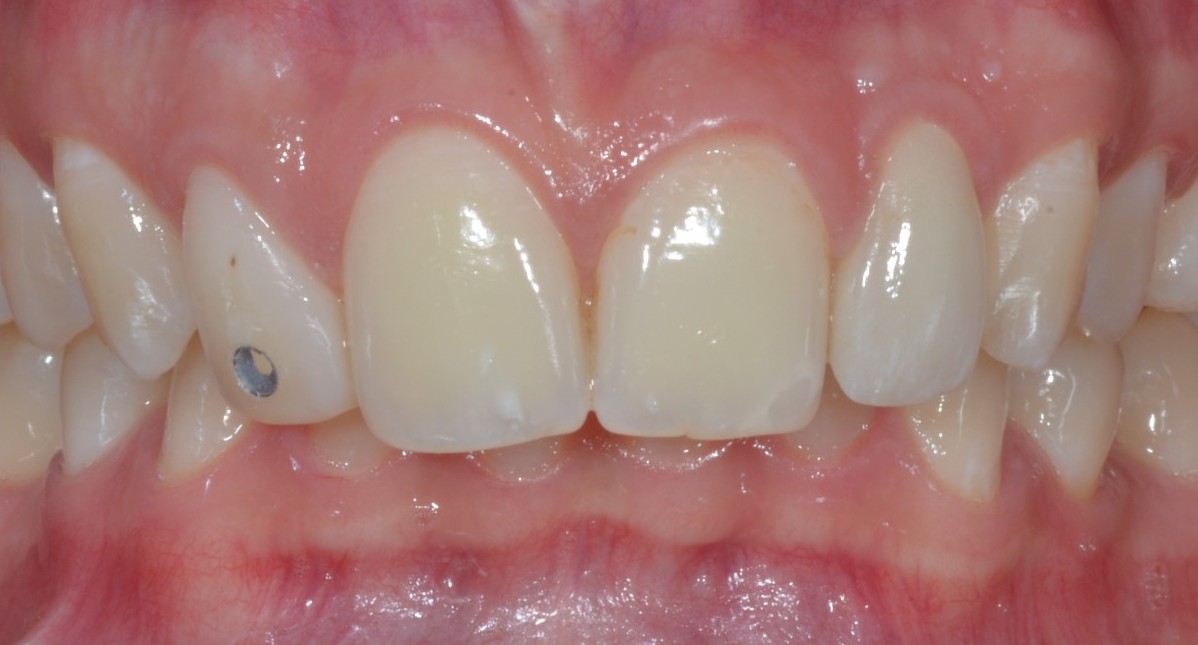

Ora Maddalena, così si chiama la ragazzina di questo dens in dente, con un piccolo allungamento di corona clinica seguito da limatura del margine incisale e una semplice otturazione di 12 e una corona in disilicato preparata su questo dens in dente, può tornare a sorridere. Ecco la foto e la rx a sei mesi dal caso finito. Tutto perfetto! Il 22 sta guarendo e le gengive e i denti stanno alla grande! Il brillantino invece ha perso il diamantino! ?